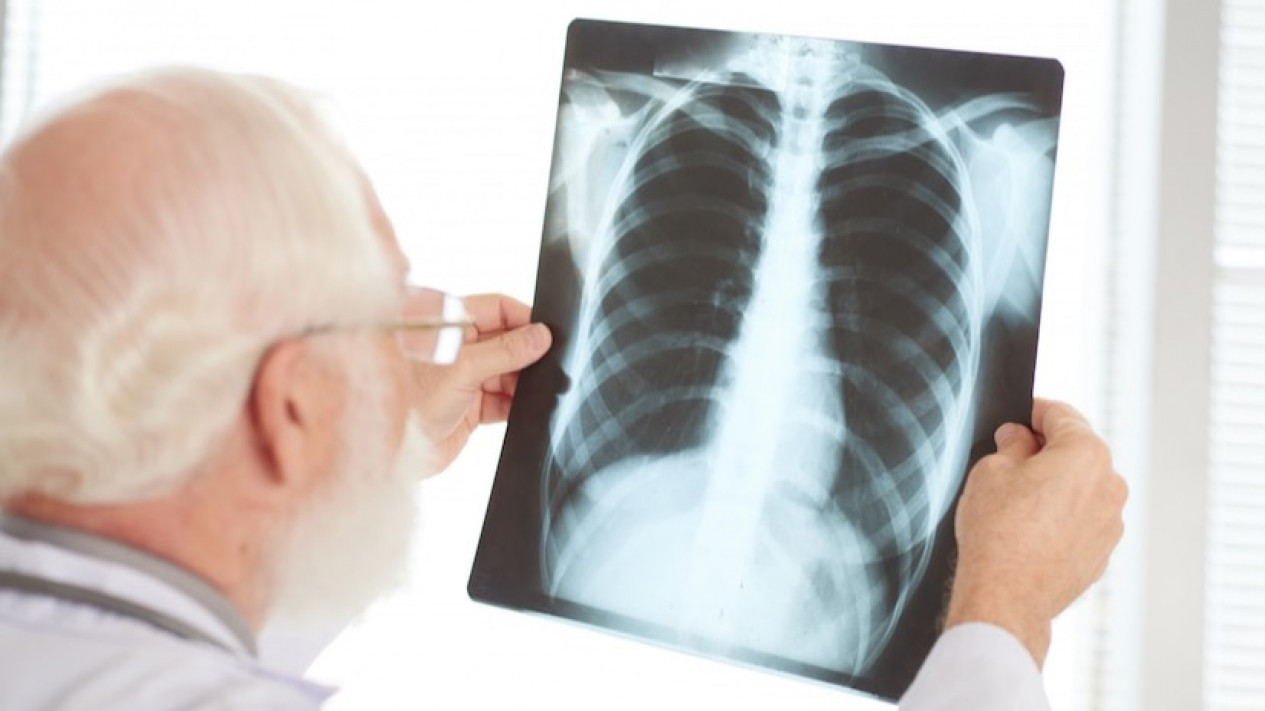

Detail Foto - Kanker Paru Bisa Disembuhkan, Asal ...

Kanker paru merupakan penyebab ketiga kanker terbanyak di Indonesia bahkan penyebab kematian peringkat pertama di antara semua jenis kanker. Pasalnya banyak - galeri foto